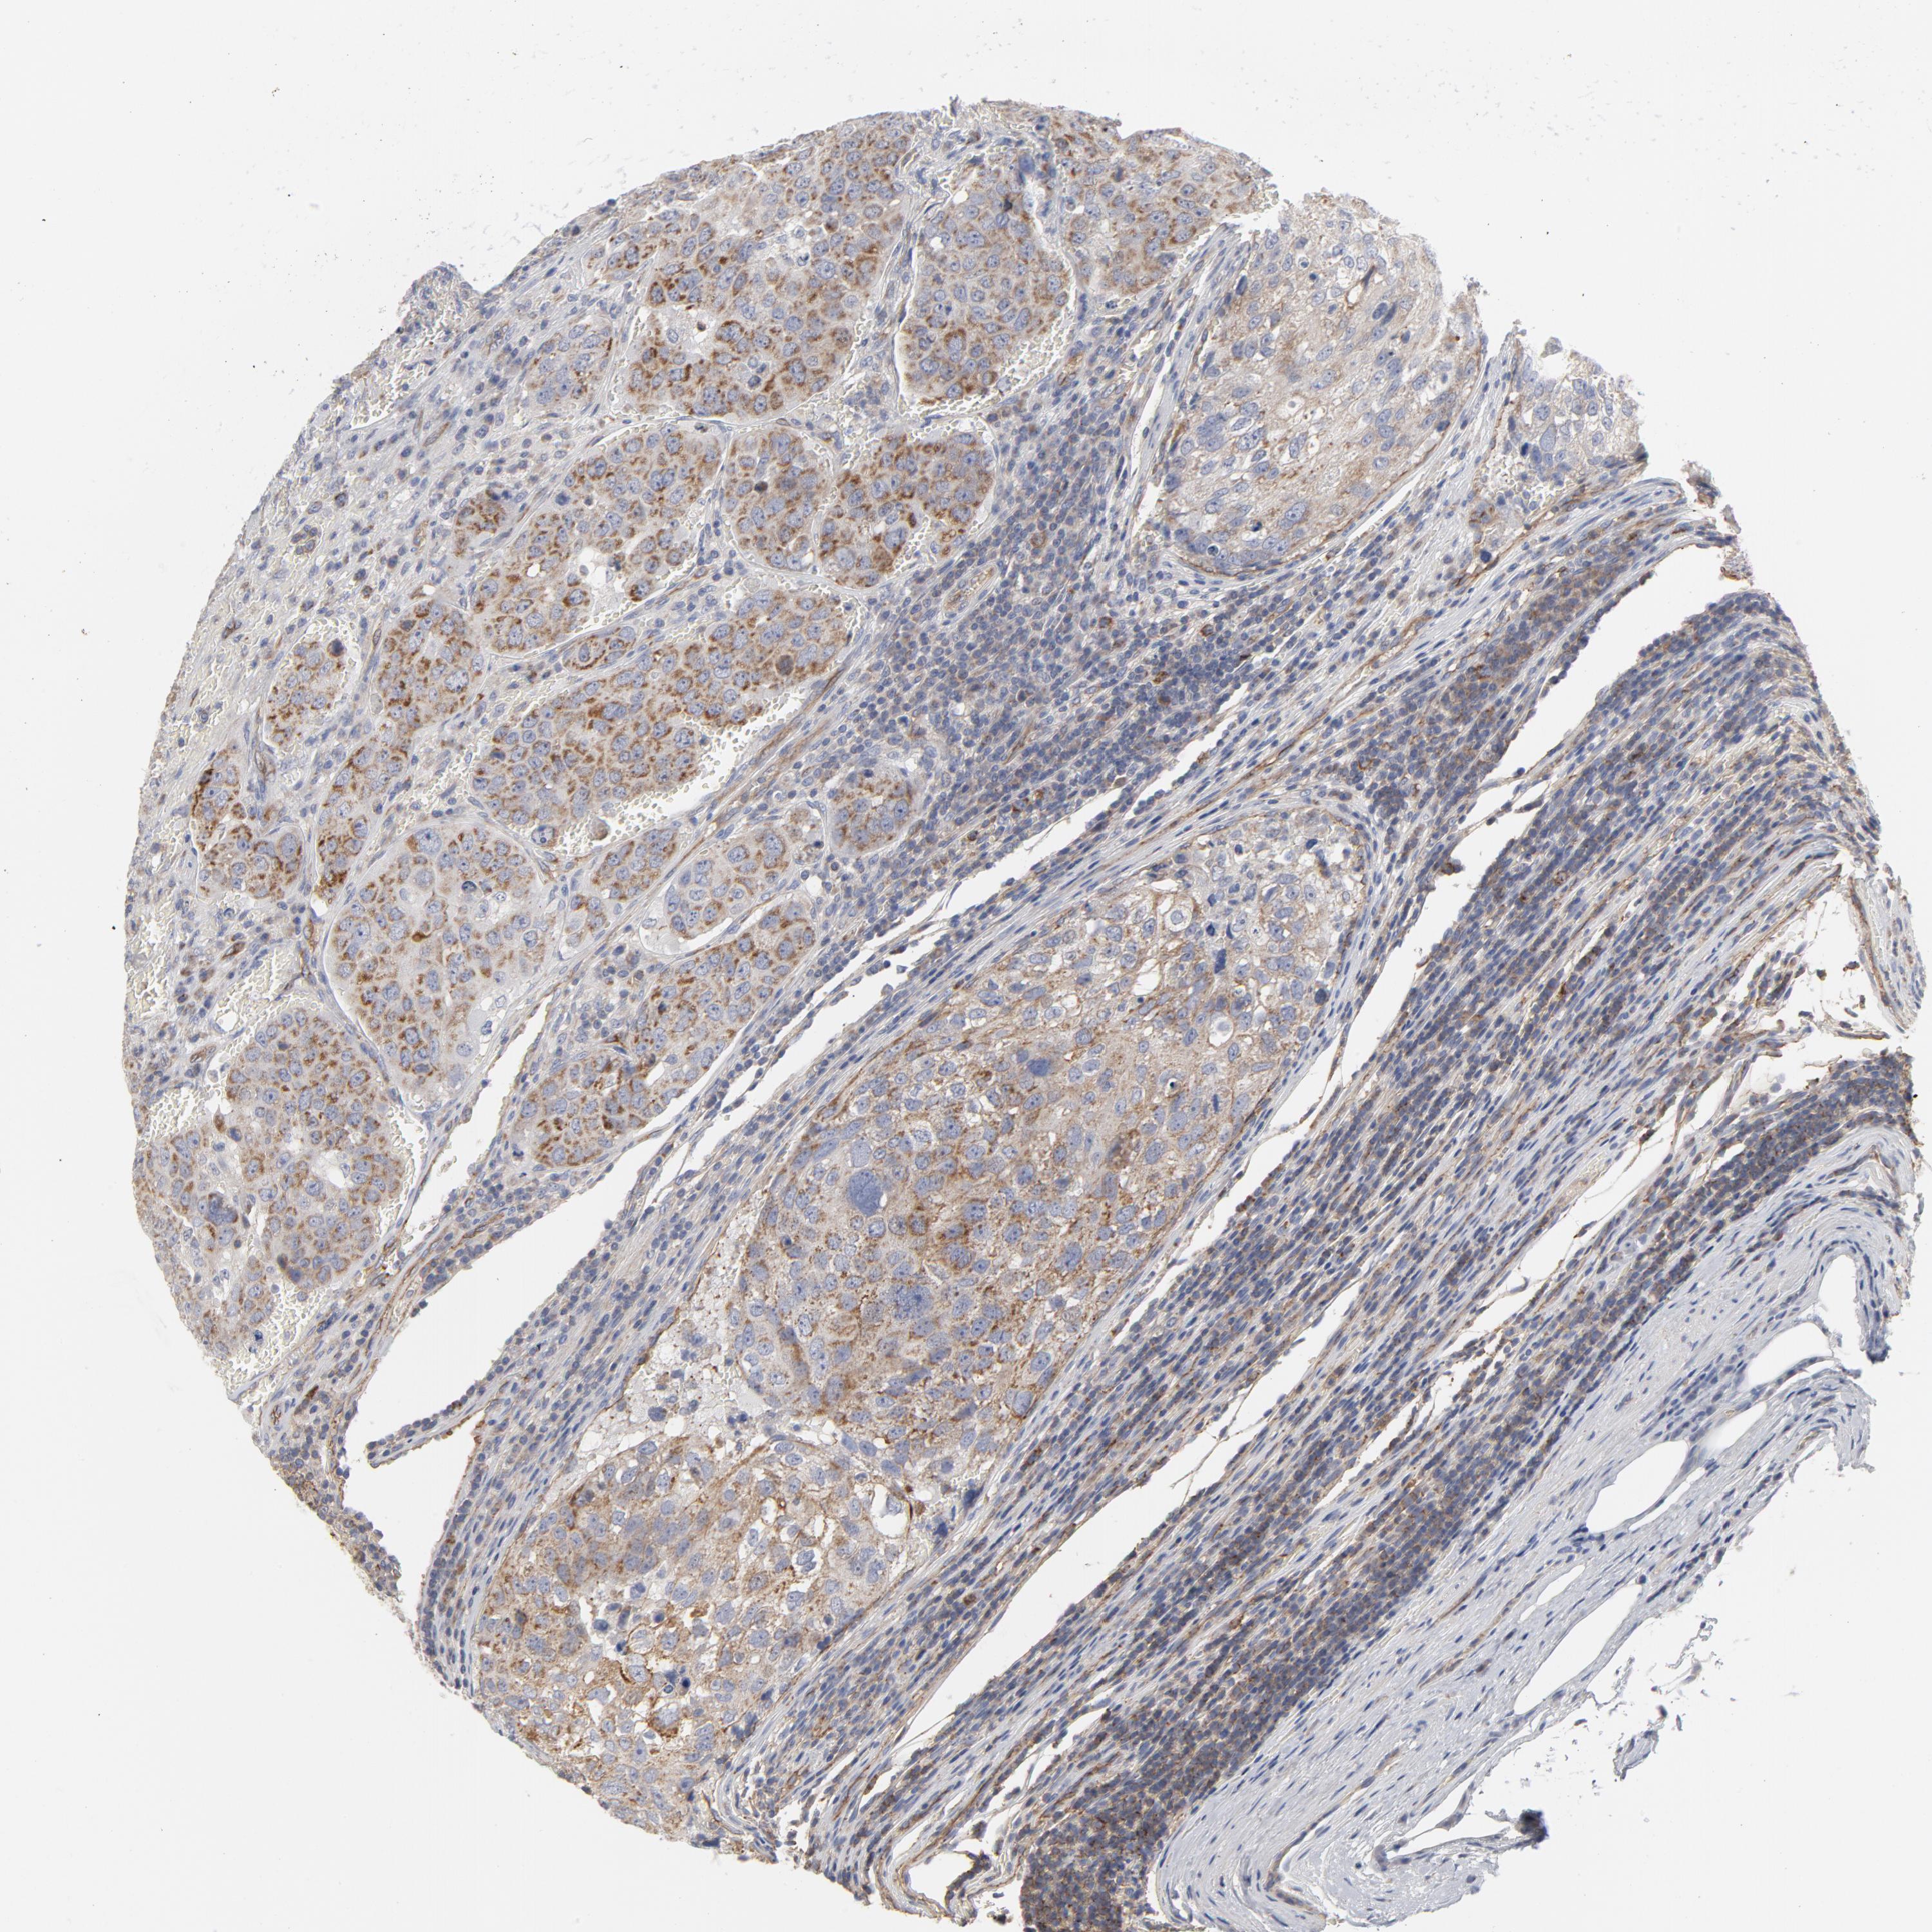

UROTHELIAL CANCER - Protein expressioni

A mouse-over function shows sample information and annotation data. Click on an image to view it in a full screen mode. Samples can be filtered based on level of antibody staining by selecting one or several of the following categories: high, medium, low and not detected. The assay and annotation is described here.

Note that samples used for immunohistochemistry by the Human Protein Atlas do not correspond to samples in the TCGA dataset.

Antibody stainingi

Antibody staining in the annotated cell types in the current human tissue is reported as not detected, low, medium, or high, based on conventional immunohistochemistry profiling in selected tissues. This score is based on the combination of the staining intensity and fraction of stained cells.

Each image is clickable and will lead to virtual microscopy that enables deeper exploration of all samples and also displays staining intensity scores, fraction scores and subcellular localization as well as patient and tissue information for each sample.

Antibody HPA003531

Staining

High

Medium

Low

Not detected

Intensity

Strong

Moderate

Weak

Negative

Quantity

>75%

75%-25%

<25%

None

Location

Nuclear

Cytoplasmic/membranous

Cytoplasmic/membranous,nuclear

Urothelial carcinoma, High grade

Urothelial carcinoma, Low grade